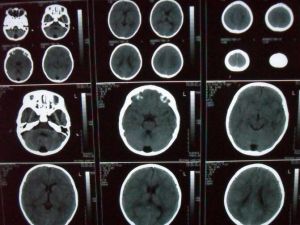

發病部位

枕大池(又稱小腦延髓池),位於顱後窩的後下部,小腦下面、延髓背側面與枕鱗下部三者之間。 向前經小腦溪通第四腦室;向前外經延髓側面通延髓池。三維斷面均可顯示。

枕大池囊腫